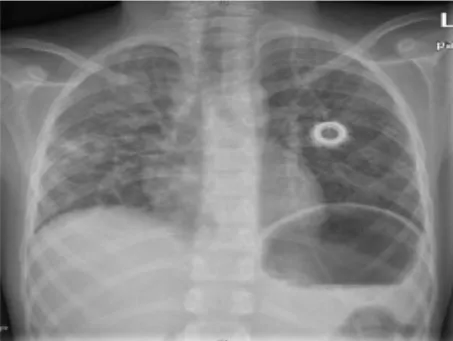

報導指出,5歲以下兒童、老年人、免疫力低下等3類人群,是感染人類間質肺炎病毒的高危險群。其中,兒童感染後容易出現毛細支氣管炎或重症肺炎,有些兒童或會出現中耳炎、腹瀉、嘔吐、出疹及發燒;老年人則可能誘發肺部感染或氣喘加重。

中國浙江大學醫院醫師指出,最近有不少兒童感染這種病毒,它全年散發,但特別好發於冬季和春季,各個年齡層都可能感染,但老人、幼童和免疫功能低下者感染風險較高。雖然只在上呼吸道,但極少數的狀況可能導致肺炎、支氣管炎或其他下呼吸道疾病。